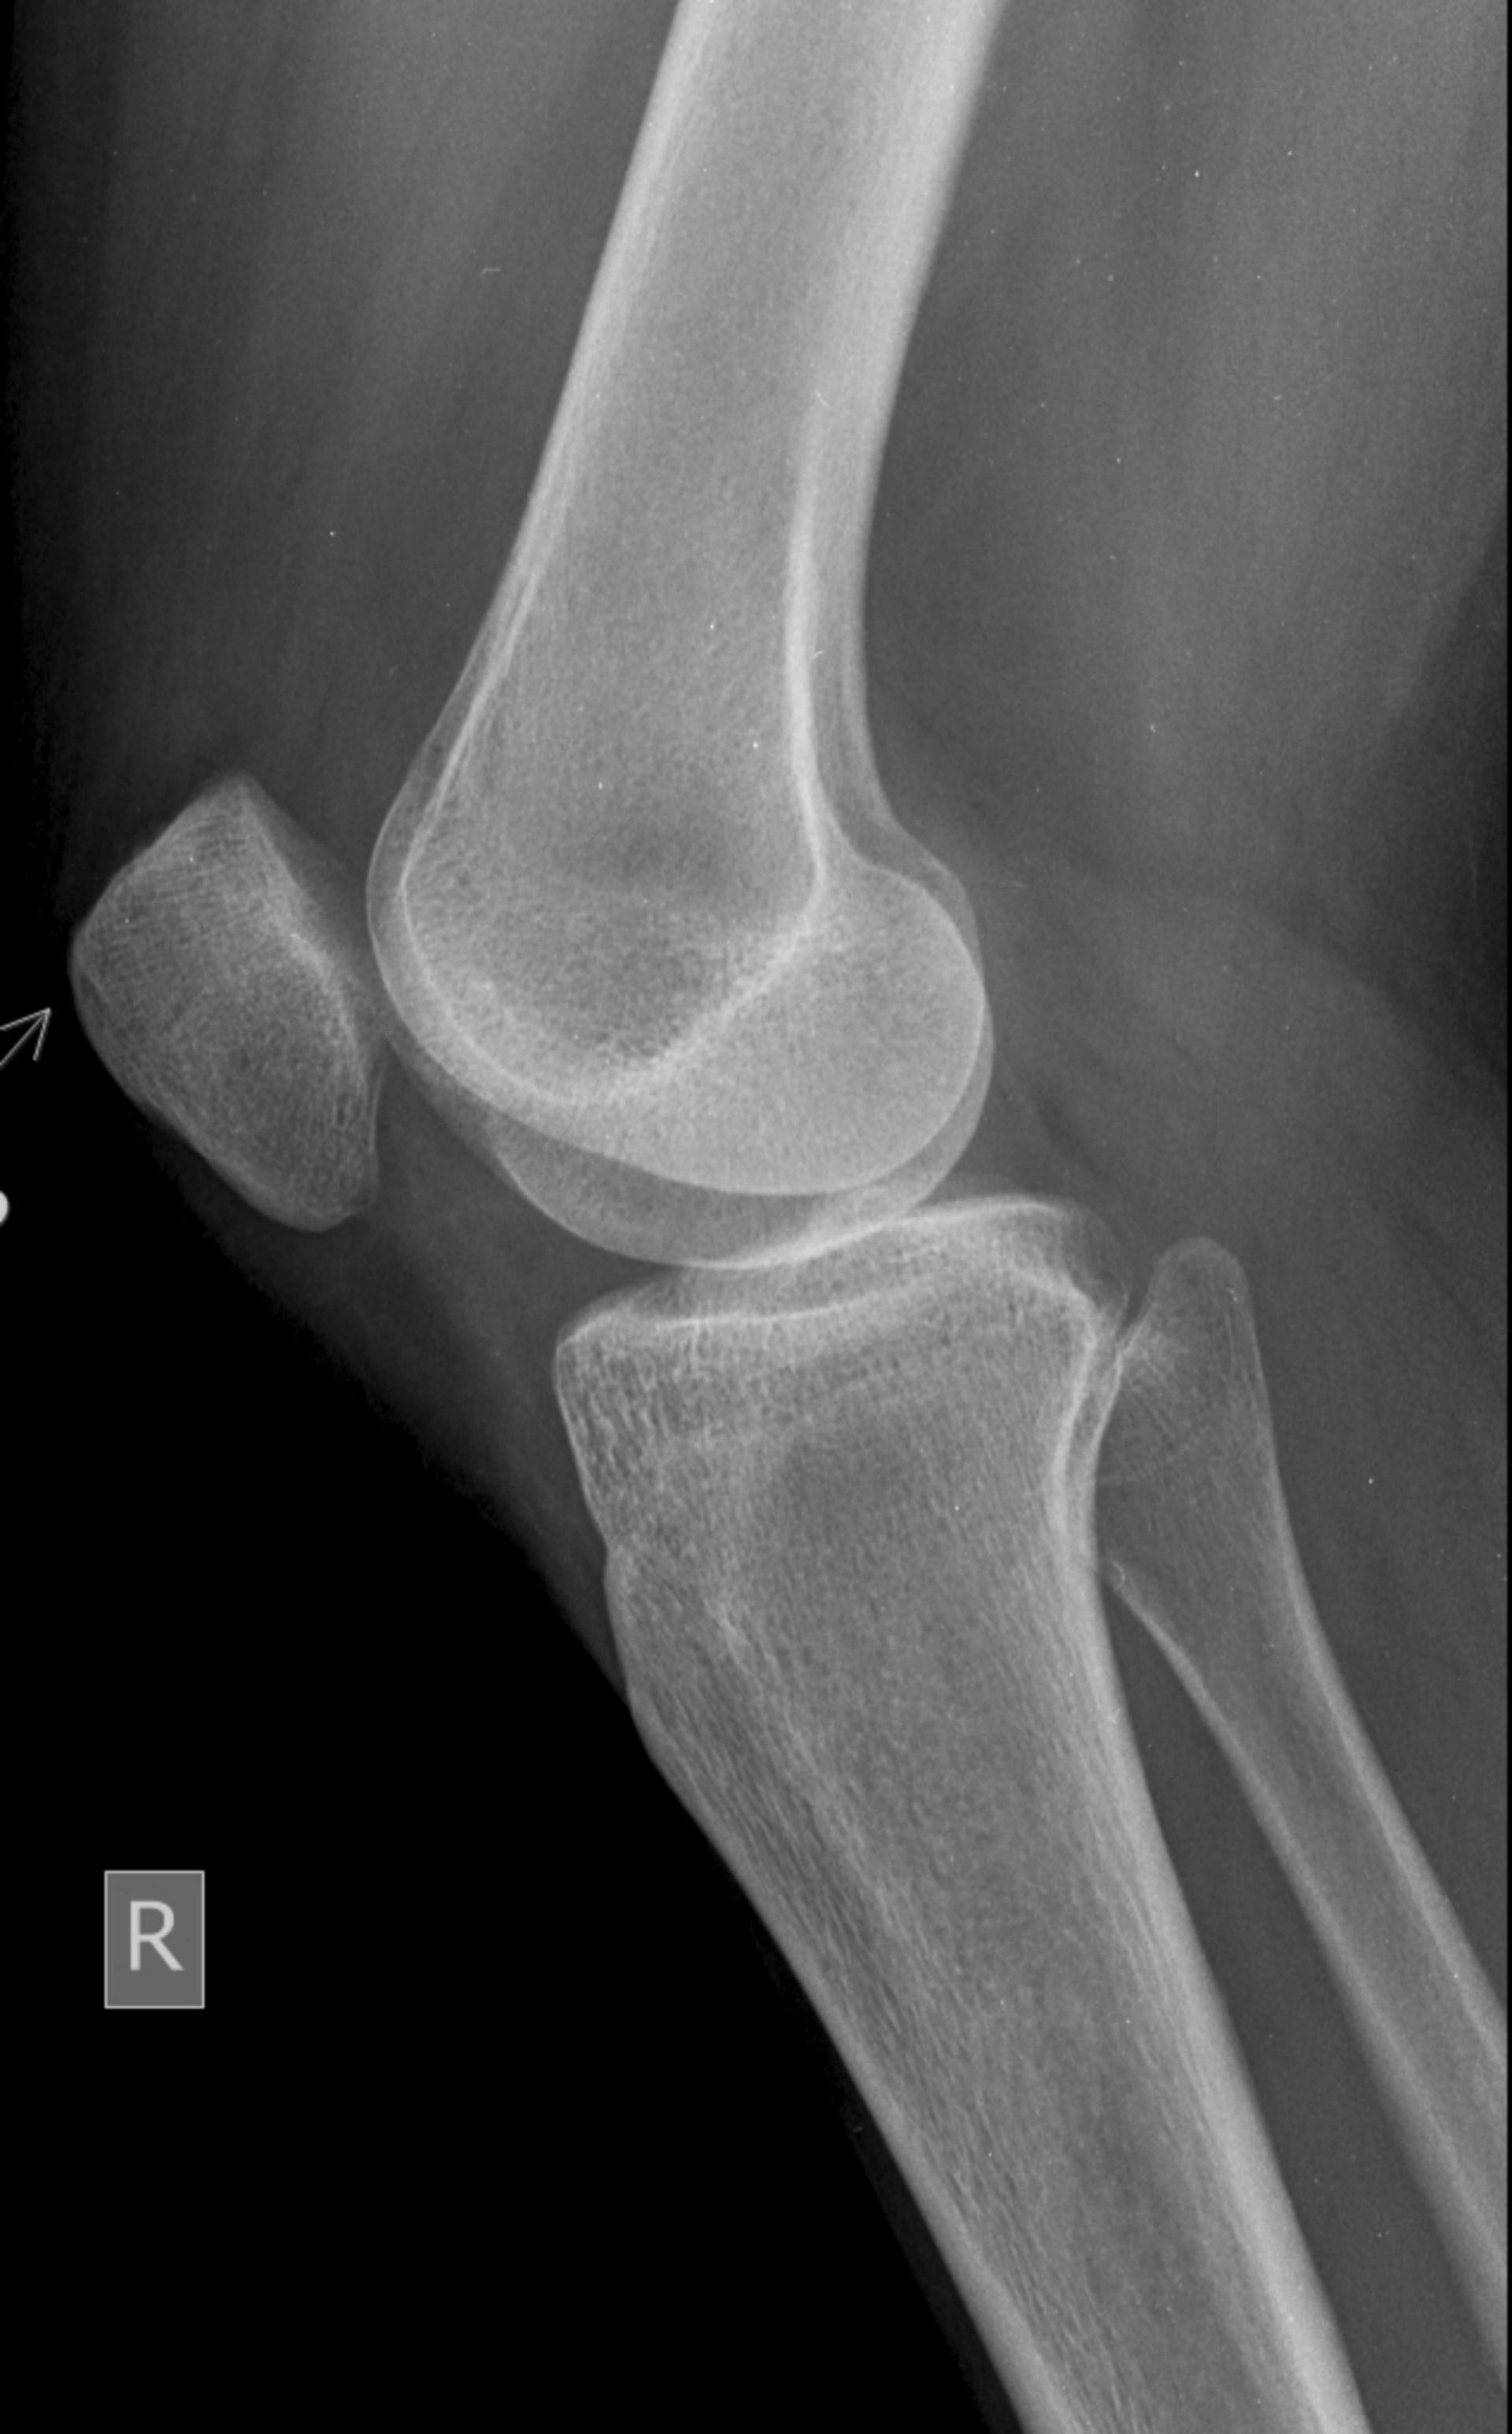

La radiologia tradizionale digitale trova applicazione in diversi ambiti clinici. Lo studio esegue radiografie mirate per lo studio di strutture ossee e articolari, adattando l’esame alle specifiche indicazioni cliniche. Tra le principali prestazioni rientrano:

- RX scheletrico (tutti i segmenti scheletrici e le sue articolazioni, con studi assiali di alcuni di essi)